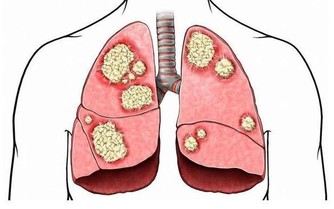

腸道清爽 人就健康

陳昌平指出,人體的腸內有許多好菌和壞菌,並且維持平衡,一旦身體因飲食、環境、壓力等因素影響,壞菌就會增加,使腸內微生態環境受到破壞,壞菌分泌的有害物質被腸道吸收,抵抗力薄弱的器官就會出毛病。